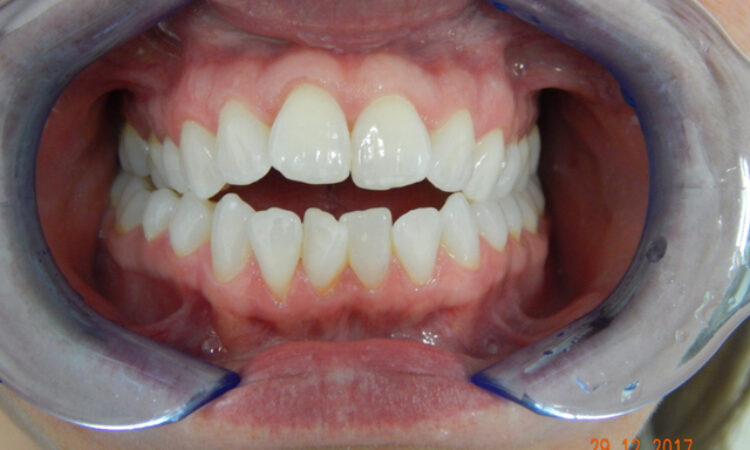

Before - puredental After - puredental

Case 18 - Invisalign®